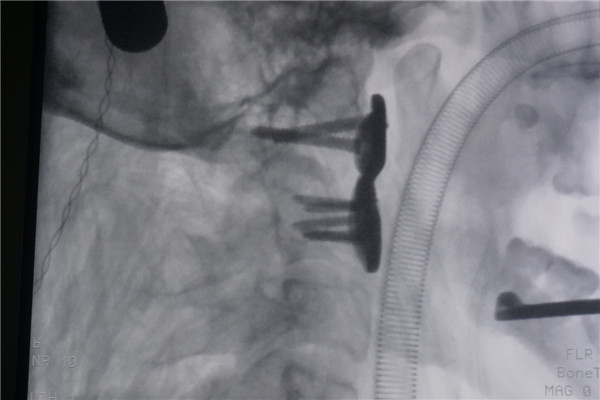

手术由贺西京、李浩鹏教授主导,王国毓副主任医师,臧全金、曹凯主治医师协助,麻醉科宋正川副主任医师麻醉。采用经鼻腔插管麻醉;麻醉完成后行头颅牵引,并颈部轻度过伸位。术中发现寰椎向前方脱位明显,寰枢椎之间瘢痕连接明显。术中软组织充分松解后仍较难复位;贺西京、李浩鹏教授果断决定采用大剂量颅骨牵引,将牵引重量增加13Kg。牵引下透视寰枢椎之间虽未达到完全复位,但是较矫形前明显好转;而且因为寰椎前弓后方骨质异常,也无法完全复位。复位后应用自行设计的3D打印寰枢椎前路钢板的固定,寰枢椎之间的脱位明显恢复,稳定性大大增强,活动性消失。术后为了保持寰枢椎之间的稳定性,采用Halo支具固定。手术历时约5小时,出血约50ml。